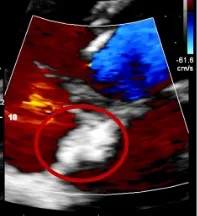

经食道心脏超声:四腔心切面缺口径宽约0.35cm,缺损边缘距二尖瓣环约2.1cm,距房顶约2.5cm,大动脉短轴切面缺口经宽0.36cm,主动脉后方无残边。双房切面缺口径约0.35cm,缺损边缘距上腔静脉约2.6cm,距下腔静脉约2.7cm。CDFI:房间隔连续中断处见左向右分流信号。

TEE可见房间隔中断出左向右分流

TEE测量缺损大小

肺动静脉CTA未见异常;经食道超声检查明确为小房缺,缺损直径约0.35cm。

TTE多切面显示封堵器双盘稳固骑跨房间隔两侧,无移位、无残余分流

TTE再次确认封堵器位置理想、双盘贴合紧密